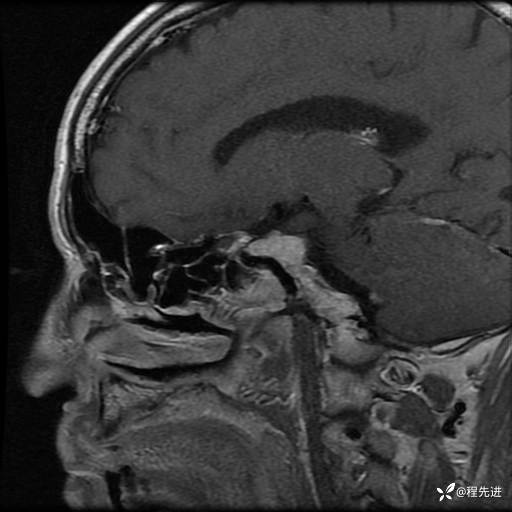

【神经】特别精彩病例|老年人,出现视物重影2月余,鞍区占位期待您的精彩解读!

患者性别:男

患者年龄:74岁

简要病史:出现视物重影2月余,未予重视,2月来症状逐渐加重

MRI平扫+增强:

T1: